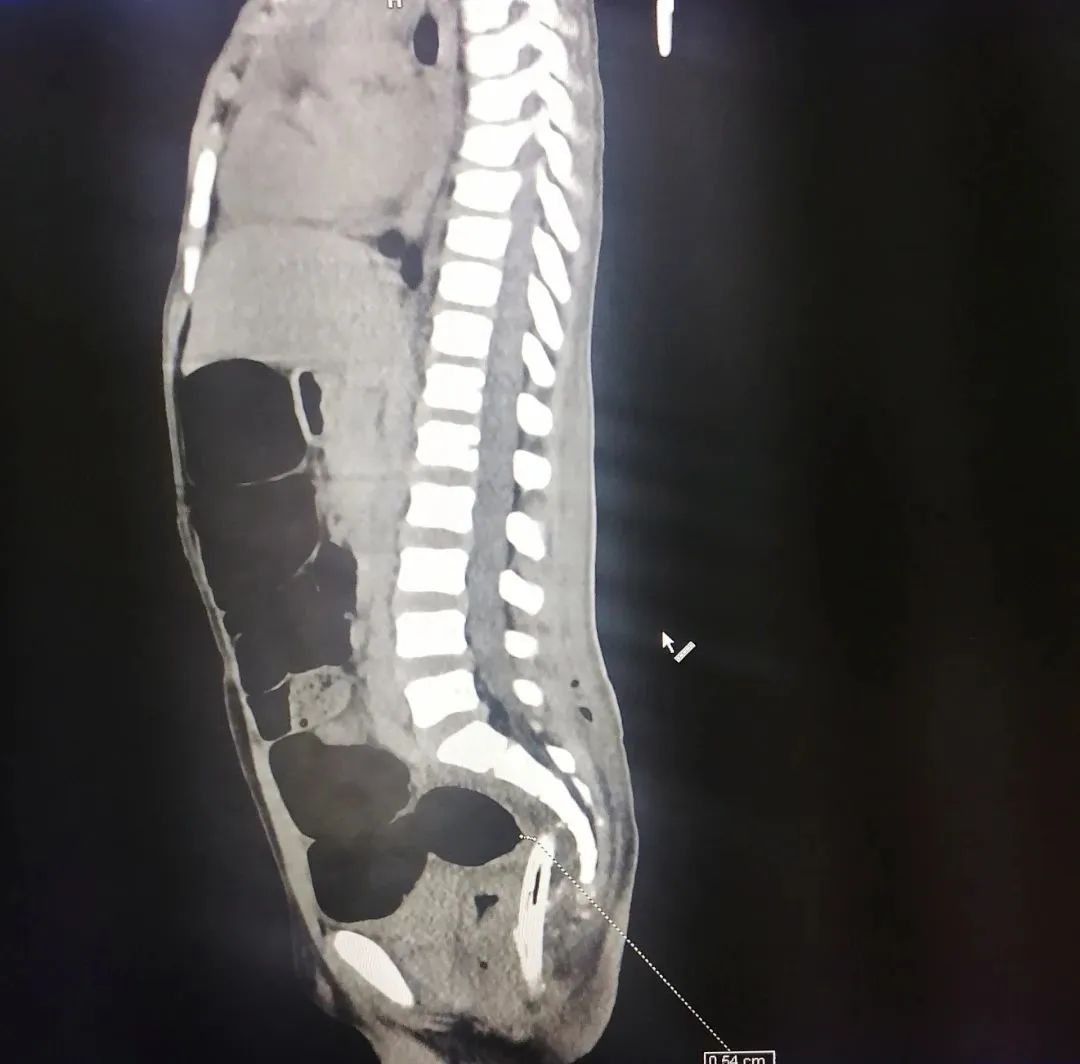

一番思索后,大家决定向岛上中国援建单位正太集团请求支援,请他们用电锯锯去孩子身上约1米的钢筋,仅剩约20厘米裸露体外,顺利保证了CT检查的进行。随后的检查发现钢筋可能损伤到脊柱,但幸运的是未伤及大血管。抢救事不宜迟。待急诊麻醉后,常来与其他中国医生通力配合,缓慢拔除孩子体内的钢筋,并置入从国内带来的专用双套管(南京军区总医院黎介寿院士发明),定期使用庆大霉素和生理盐水等冲洗引流,保存引流通畅,防止体内大面积感染。